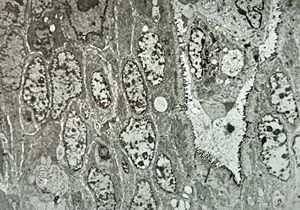

M,50y. | Pneumocystis carinii - lung